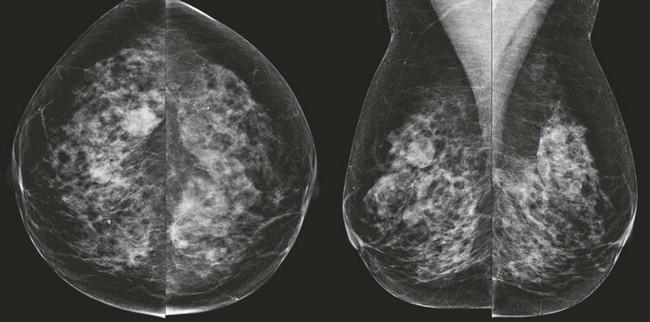

FIGURE 8-3 Multiple Fibroadenomas.

Screening mammogram on a 50-year-old woman. There are multiple bilateral masses, most with coarse calcifications typical of fibroadenomas. The noncalcified masses (arrows) likely represent fibroadenomas as well. The findings showed no suspicious changes for over 4 years.